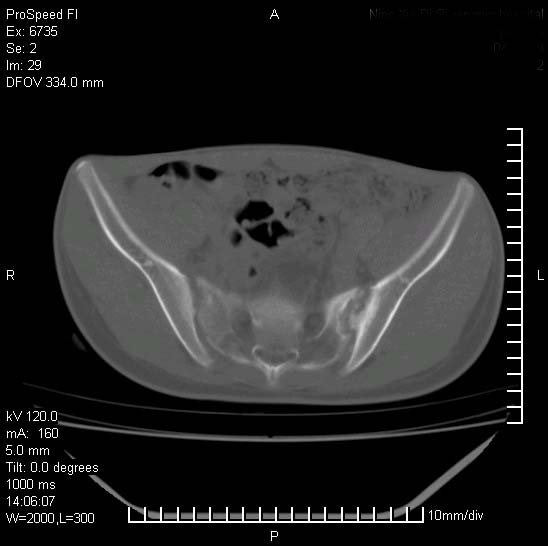

患者自诉胯部疼痛两年余,在当地服用中药,半月前至本院考虑骶髂关节结核,给予抗痨治疗。现发展至右下肢疼痛明显,活动受限,以膝关节处明显,拍膝关节平片无明显异常。

两侧骶骼关节改变,考虑强直性脊炎

左侧骶髂关节面限局性骨破坏,边缘硬化关节腔见钙化物;不出外tb

右侧骶髂关节也有类似改变,只是较左侧轻,首先考虑强直性脊柱炎,不除外结核,建议作hla-b27检查。

典型强脊炎改变,髋关节亦有累及

符合强直性脊柱炎表现。